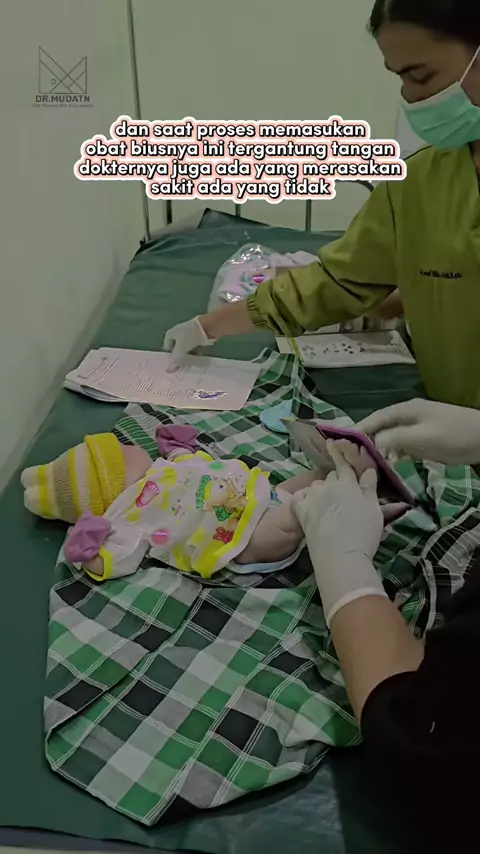

Dok saya melahirkan anak ke 2 dengan cara di induksi kok saya lebih kesakitan yah #induksimelahirkan #induksipersalinan #delivery #spontandelivery #infokesehatan #samasamabelajar